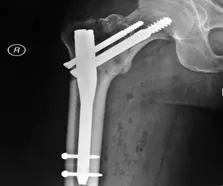

- L’ostéosynthèse : C’est le fait d’insérer une vis pour stabiliser la fissure du col du fémur, à condition que la densité osseuse soit suffisante.

-

Le vissage dynamique de la hanche : C’est une plaque de métal qui est placée dans la partie supérieure de la jambe accompagné d’une vis fixée sur la tête du fémur.